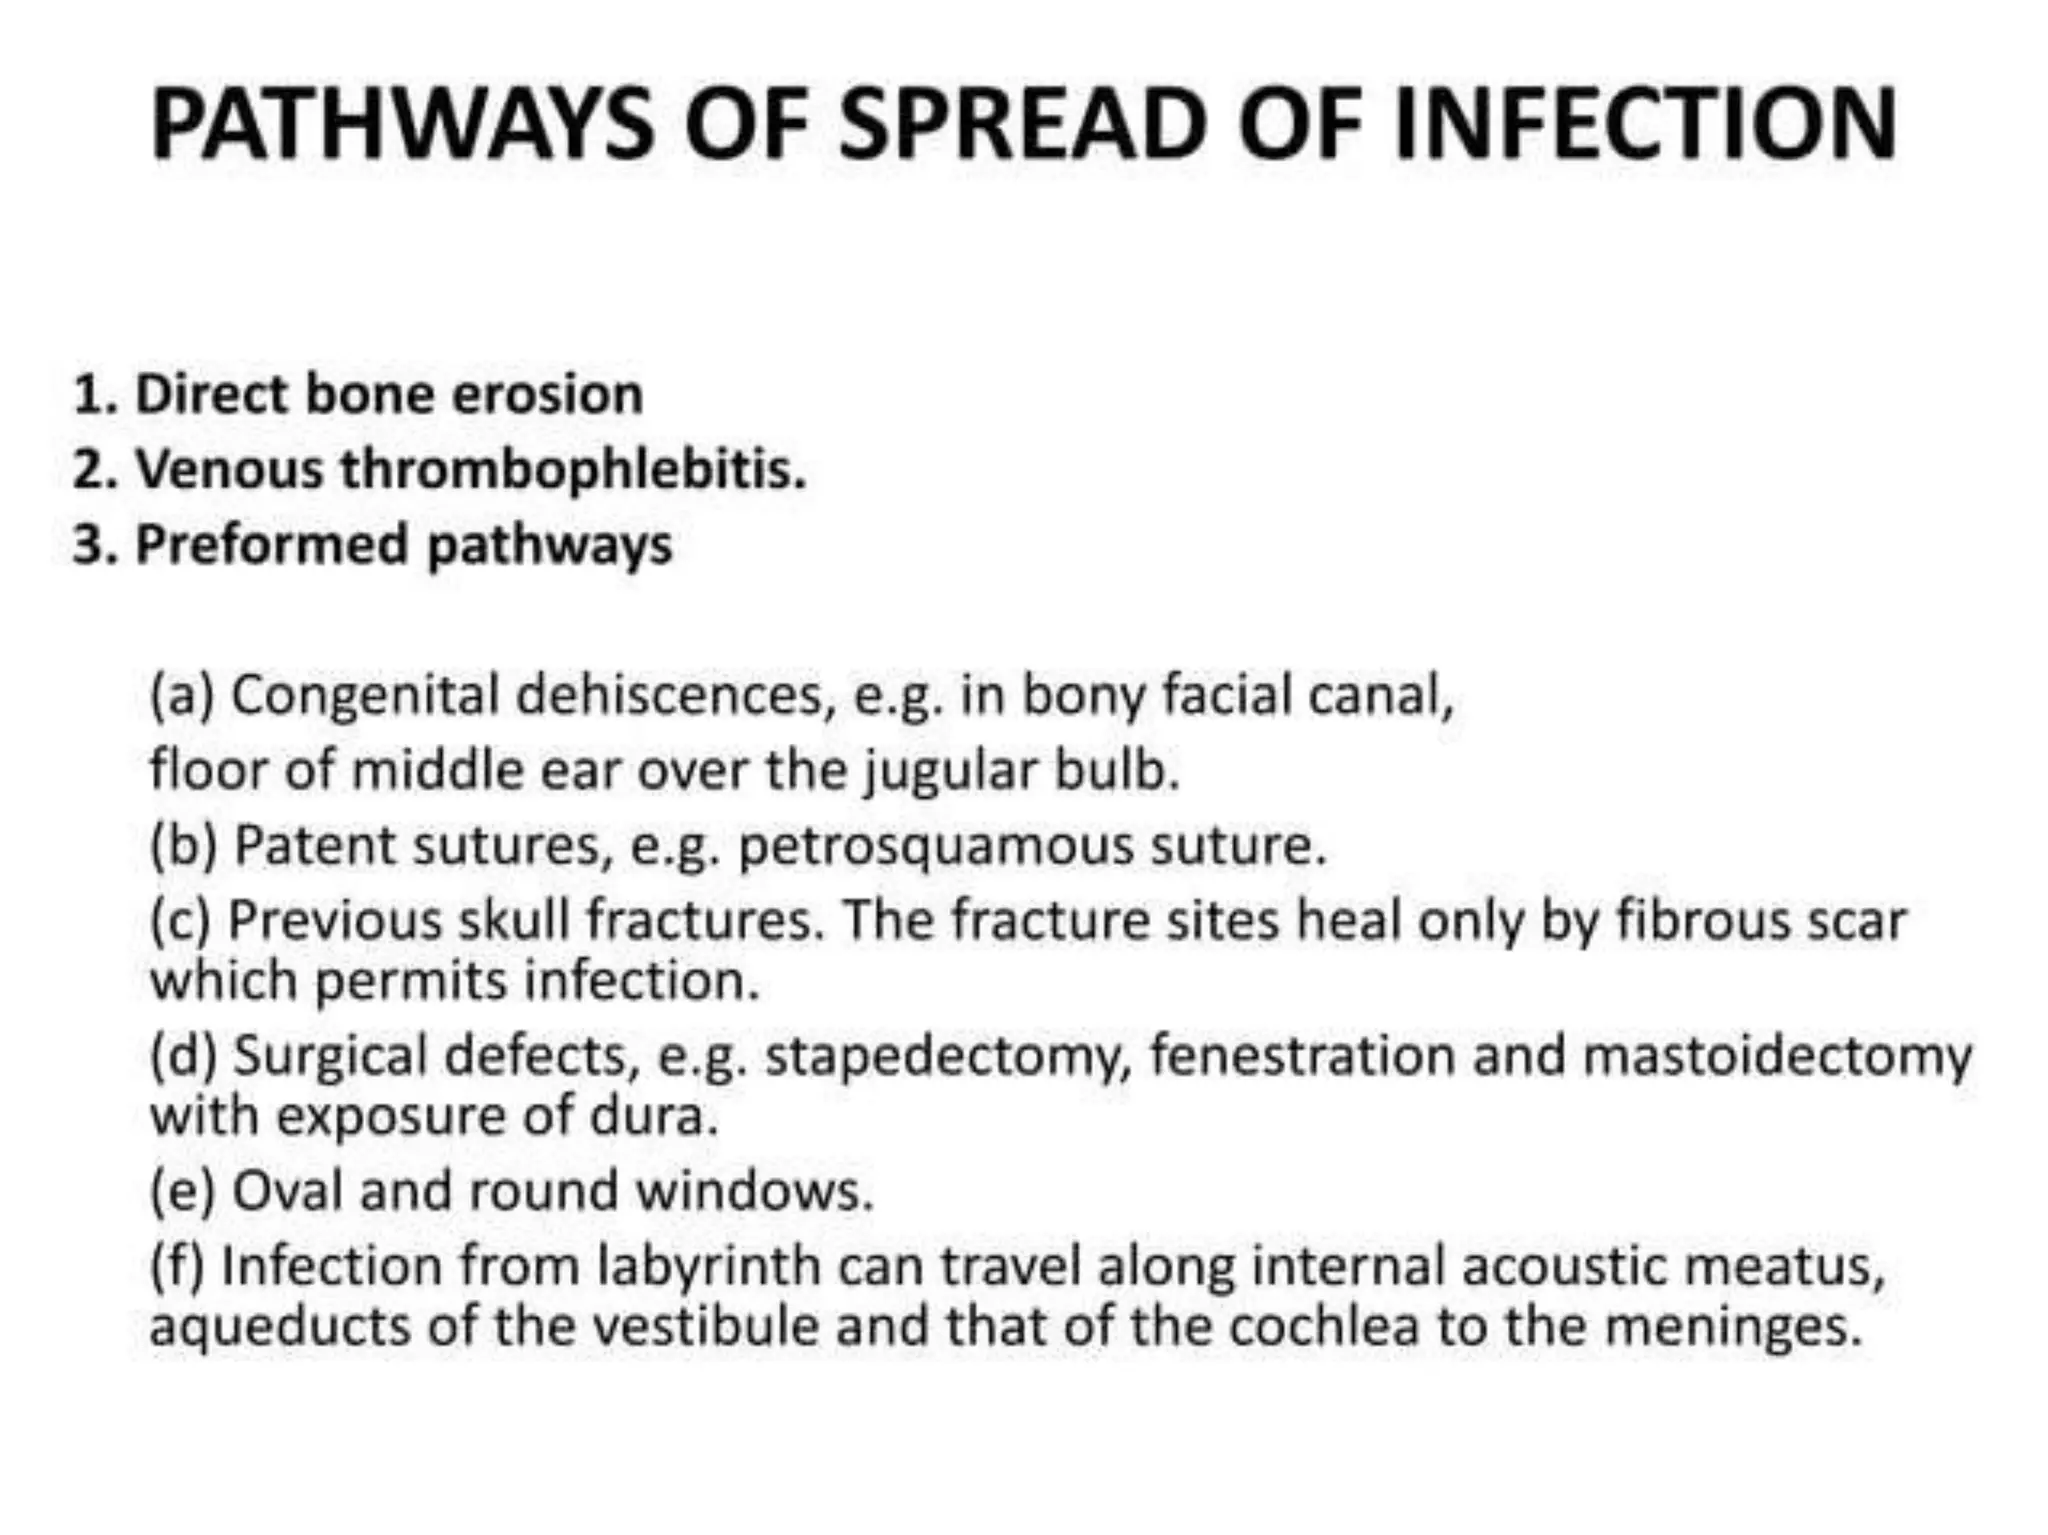

Chronic otitis media is a chronic inflammation of the middle ear and mastoid cavity that presents with recurrent ear discharge through a perforated eardrum. It has several subtypes depending on the state of the eardrum perforation and epithelium. It can be caused by prior acute otitis media, genetics, environment, eustachian tube issues, gastroesophageal reflux disease, craniofacial abnormalities, or immune deficiency.